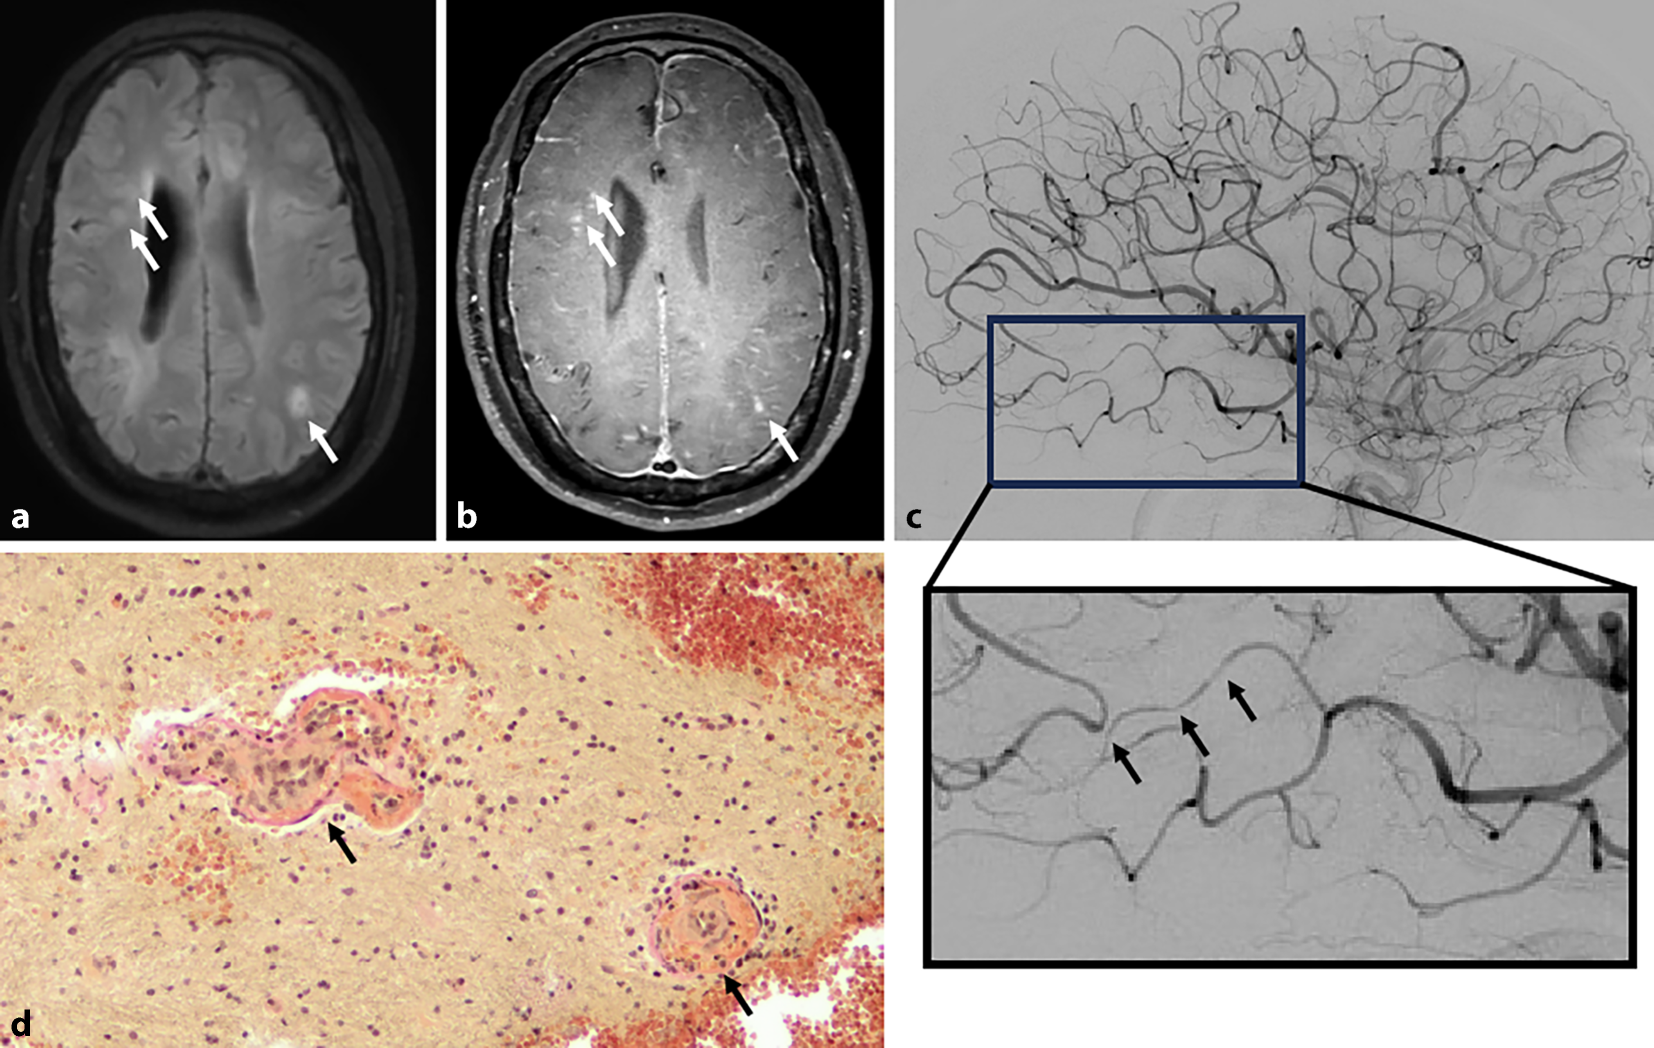

Magnetresonanztomographisch zeigen sich typischerweise multifokale Läsionen in der weißen Substanz, gadoliniumaufnehmende Läsionen und ein leptomeningeales Enhancement [6]. Gradientenechosequenzen können petechiale Hämorrhagien darstellen. Das sog. „black-blood imaging“ kann bei der MV/LV-PACNS den klassischen Befund einer konzentrischen, segmentalen Kontrastmittelaufnahme ergeben [7], birgt jedoch das Risiko falsch-positiver Befunde. Wichtig in der Verlaufsdiagnostik der PACNS ist, dass eine Kontrastmittelaufnahme der Gefäßwand trotz Immuntherapie persistieren kann und nur partiell auf Rückfälle hinweist [7]. Abb. 1 zeigt typische MR-tomographische, angiographische und histopathologische Befunde.

Abb. 1

Charakteristische Befunde bei Patienten mit primärer Angiitis des zentralen Nervensystems (PACNS). a Magnetresonanztomographie (MRT) mit FLAIR(„fluid attenuated inversion recovery“)-Sequenz, die multiple demyelinisierende Läsionen aufzeigt. b MRT unter Verwendung von Black-blood-Sequenzen, welche einerseits eine teilweise deutliche Kontrastmittelaufnahme der Läsionen demonstrieren (Pfeile) und andererseits eine ausgeprägte Kontrastmittelanreicherung der Pachy- und Leptomeningen zeigen, als Indikator der floriden Entzündung. c Digitale Subtraktionsangiographie (DSA), die multiple Kaliberschwankungen aufweist, exemplarisch im vergrößerten Bildausschnitt durch Pfeile markiert. d Elastica-van-Gieson(EvG)-Färbung eines Biopsats mit durch Pfeile gekennzeichneten Blutgefäßen, die Gefäßwandnekrose und einzelne Lymphozyten in der Gefäßwand zeigen (Vergr.: 200-fach)